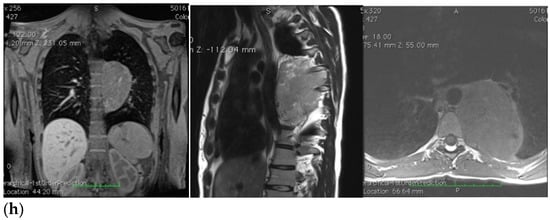

Therefore, her GP prescribed a chest X-ray, which revealed a voluminous opacity in her posterior mediastinum on the left (Figure 1a); subsequently, the GP referred the patient to a thoracic surgeon, who prescribed a series of imaging (Figure 1b–h) tests to biologically circumscribe the lesion, in order to evaluate its metabolic activity and its eventual malignancy. After these further investigations, the patient’s histopathological diagnosis was of poorly differentiated neuroblastoma ALK + (IIC), I stadium [,]. The patient was inserted in the operating room schedule for surgical excision.

Figure 1.

(a–h) Imaging assessments for pre-surgical evaluation. (a) X-ray scans. (NOTE: Voluminous opacity in the posterior mediastinum on the left, with a major axis of about 12 cm). (b) Thorax CT scan with Iodixanol. (NOTE: Solid, oval-shaped tumour in the left posterior mediastinum, measuring 8 × 5.5 cm. Anteriorly, the mass pressed the left main bronchus from behind, while medially it displaced the thoracic aorta—sitting directly on the metamers T5 to T8, and compressing the hemiazygos vein. The mass also went through the intervertebral foramen, between T6 and T7, and partially through the VI and VII intercostal spaces; laterally, it caused dystelectasis of the lung parenchyma. The NB had an irregular density, with innumerable small foci of calcification, and areas of slightly blurred impregnation of the contrast medium). (c) Tracheobronchoscopy. (NOTE: Left lower lobe bronchus with a luminal narrowing, resembling an extrinsic compression. In detail: left lower lobe bronchus, left main bronchus, trachea and carina). (d) Thorax MRI with Gadoteridol. (NOTE: Presence of a mass with maximum dimensions of approximately 7.5 × 5.5 cm axially and 10 cm of craniocaudal extension, limited by a plane passing from upper T6 to lower T9. Extension up to the ipsilateral lung, which caused a moderate compression and a slight compressive effect, also on the left sections of the heart (in particular the atrium). Slight anterior displacement of the ipsilateral pulmonary hilum structures; the neoplasm also came into contact with the aorta. The tumour went through the left T6–T7 intervertebral foramen—taking up space at the foraminal level, not at the level of the spinal canal—and it also extended up the corresponding intercostal space; it was compatible with a lesion originating from the nerve sheath arising from the T6–T7 foraminal region). (e) Total-Body PET/CT. (NOTE: Presence of an increased glucose metabolism lesion in the posterior mediastinal area, showing a necrotic portion and a metabolically more active portion, located in the medial side and infiltrating the posterior arch of the 6th left rib). (f) Thorax CT scan with Lopromide. (NOTE: Minor volumetric increase of the known space-occupying lesion, which maintained similar densitometric characteristics, clear limits, and maximum diameters equal to 8.5 × 6 cm on the transverse plane, with a maximum longitudinal extension of 11 cm. The solid component which went through the intercostal space between T6 and T7 was substantially unchanged. Absence of pleural or pericardial effusion). (g) Total-body scintigraphy with metaiodobenzylguanidine. (NOTE: The examination confirmed that the neoplasm was confined to the mediastinum only. The area of greater contrast medium enhancement corresponded to the left hemithorax, in particular, to the left posterior mediastinal region, from T6 to T9). (h) Thorax MRI with Gadoteridol. (NOTE: Slight increase in size of the known space-occupying lesion in the posterior mediastinum (85 × 60 × 103 mm vs. 80 × 55 × 100 mm). At T6–T7 level, the mass occupied some left foraminal canal space. Next to the known lesion, pleural effusion thin layer (maximum thickness of 11 mm)).